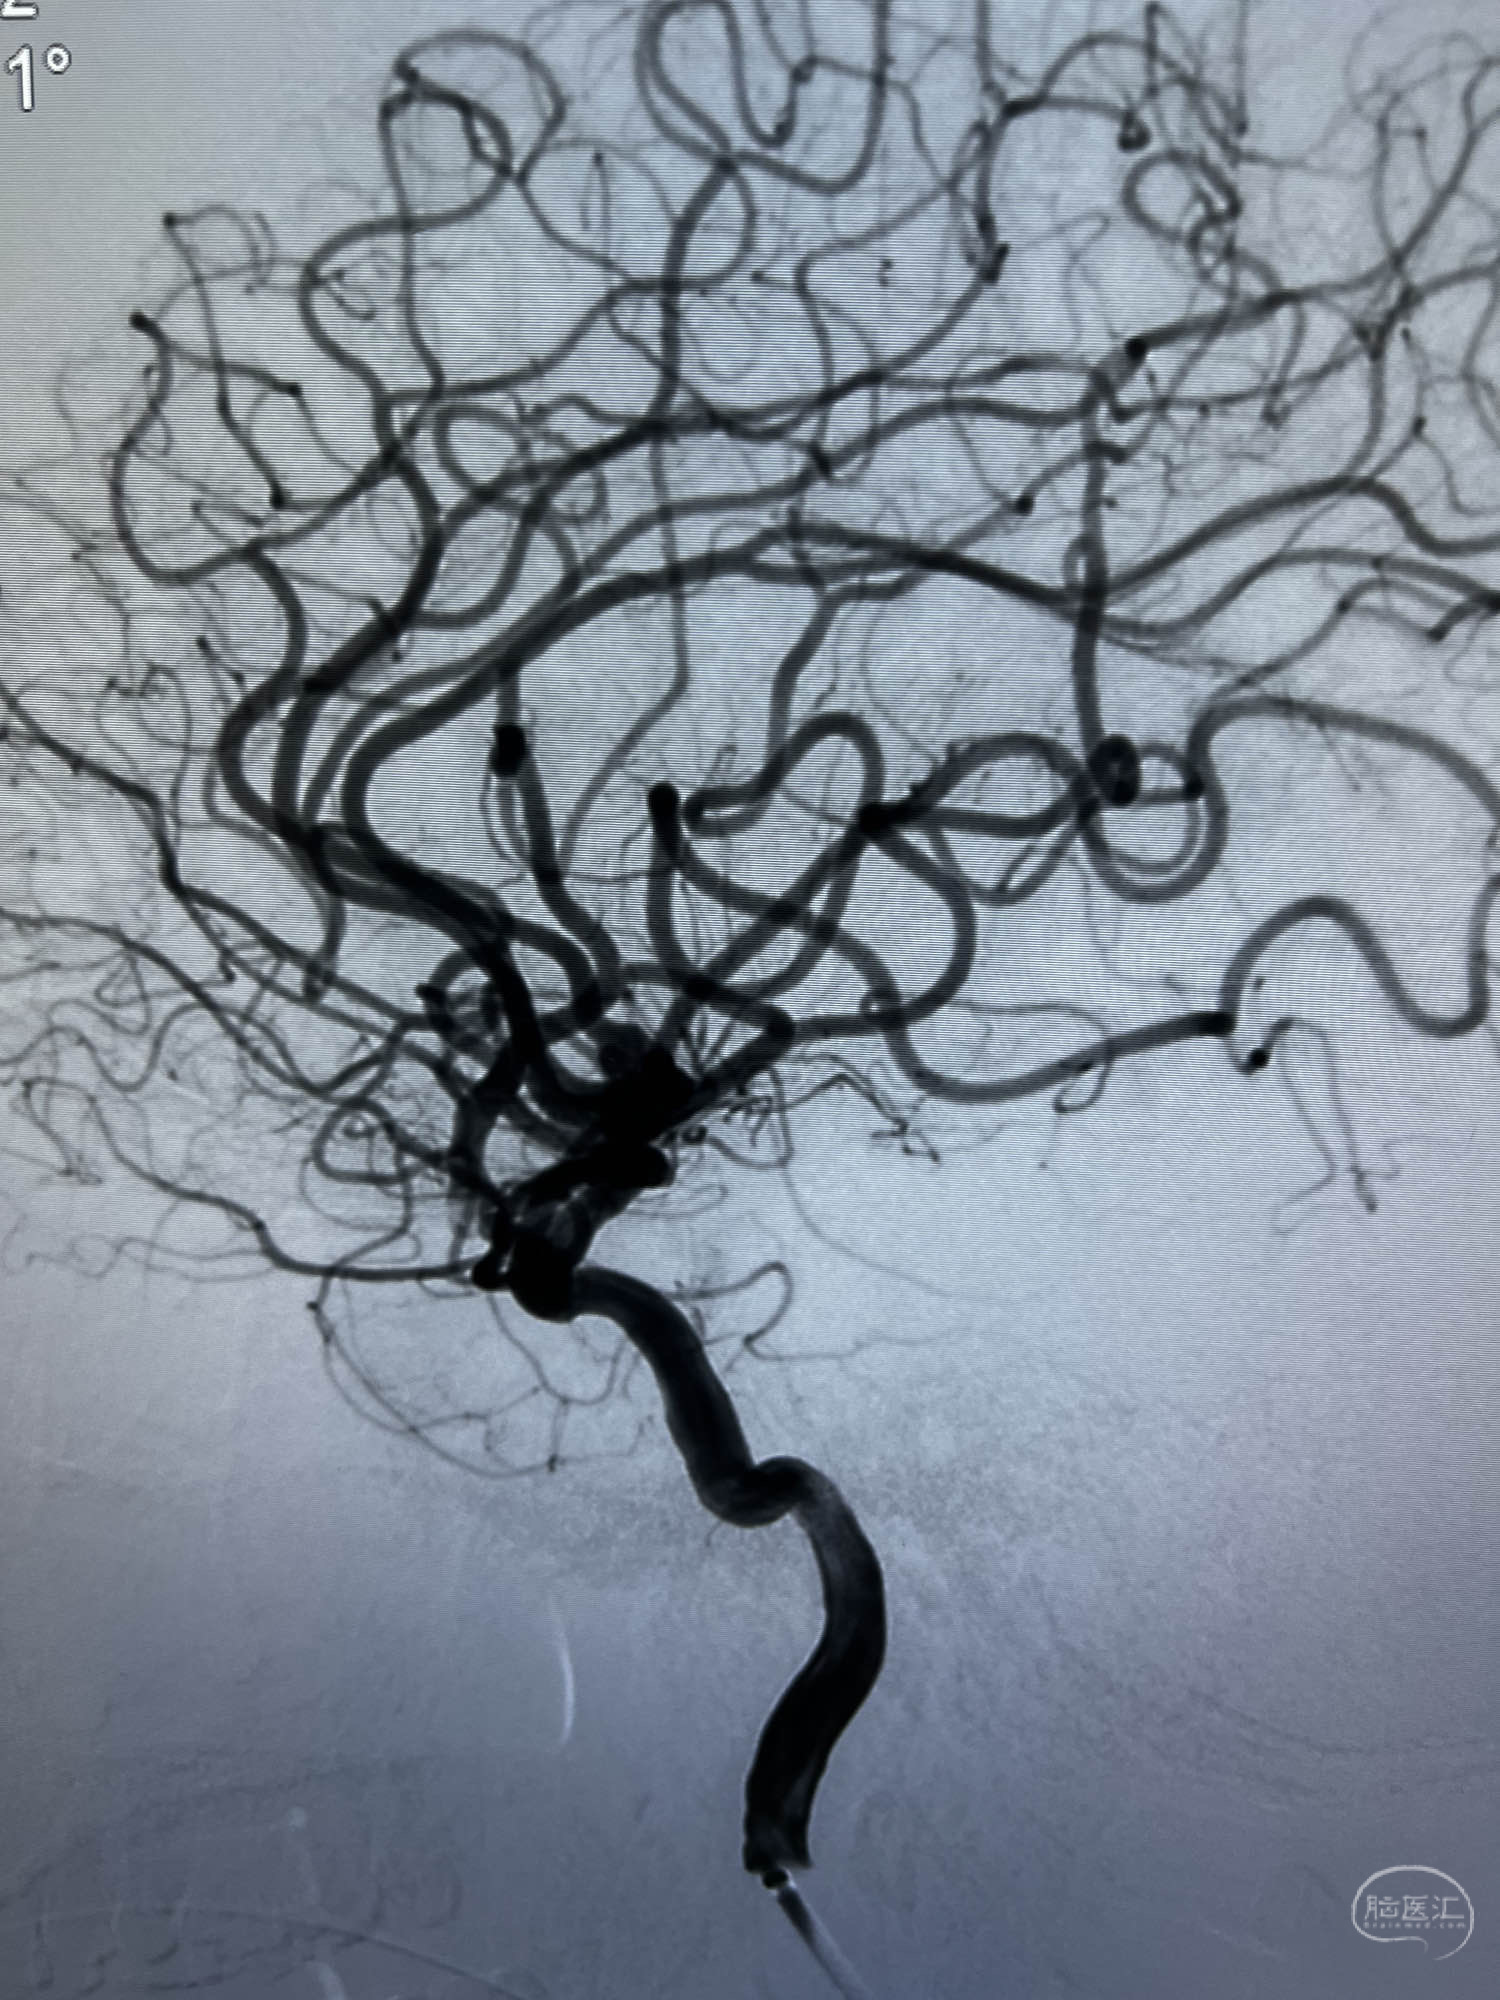

患者:LXS,M53Y,以“间断头晕头痛1周”为主诉入院,既往有高血压病及长期吸烟史。在当地医院行头颅CT未见异常,头颅MRA示右侧大脑中动脉M1段末端动脉瘤,左侧颈内动脉闭塞,交通动脉开放。

DSA示:左侧颈内动脉眼动脉段以远闭塞,后交通动脉开放,椎基底动脉通过后交通动脉代偿左侧大脑中动脉区域,右侧发出双侧大脑前动脉,右侧大脑中动脉M1末端宽颈动脉瘤,大小约4.3mmx4.6mm。

WEB瘤内扰流装置5mmx3mm经过“种子、萌芽、开花”三个阶段,打开后良好贴壁,动脉瘤内血液滞留,载瘤动脉通畅。WEB一步到位,通过瘤内扰流的方式起到栓塞动脉瘤的作用,避免了应用支架保护分支血管,简化了操作步骤,降低了术中血栓及出血的风险。